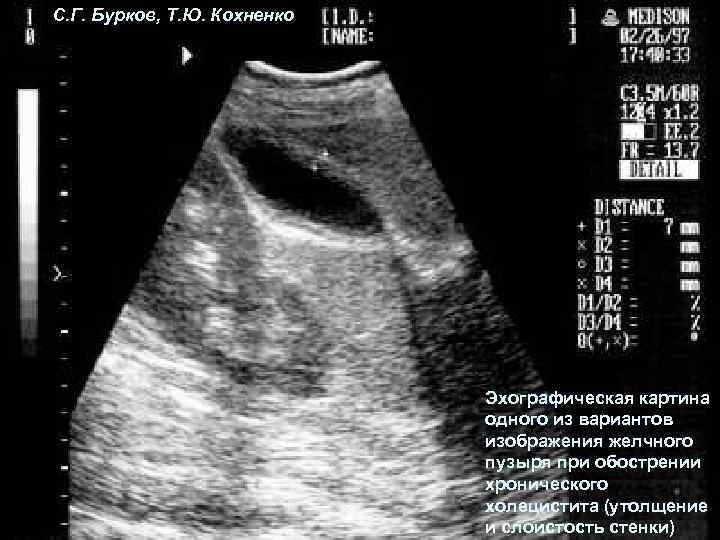

С. Г. Бурков, Т. Ю. Кохненко Эхографическая картина одного из вариантов изображения желчного пузыря при обострении хронического холецистита (утолщение и слоистость стенки)